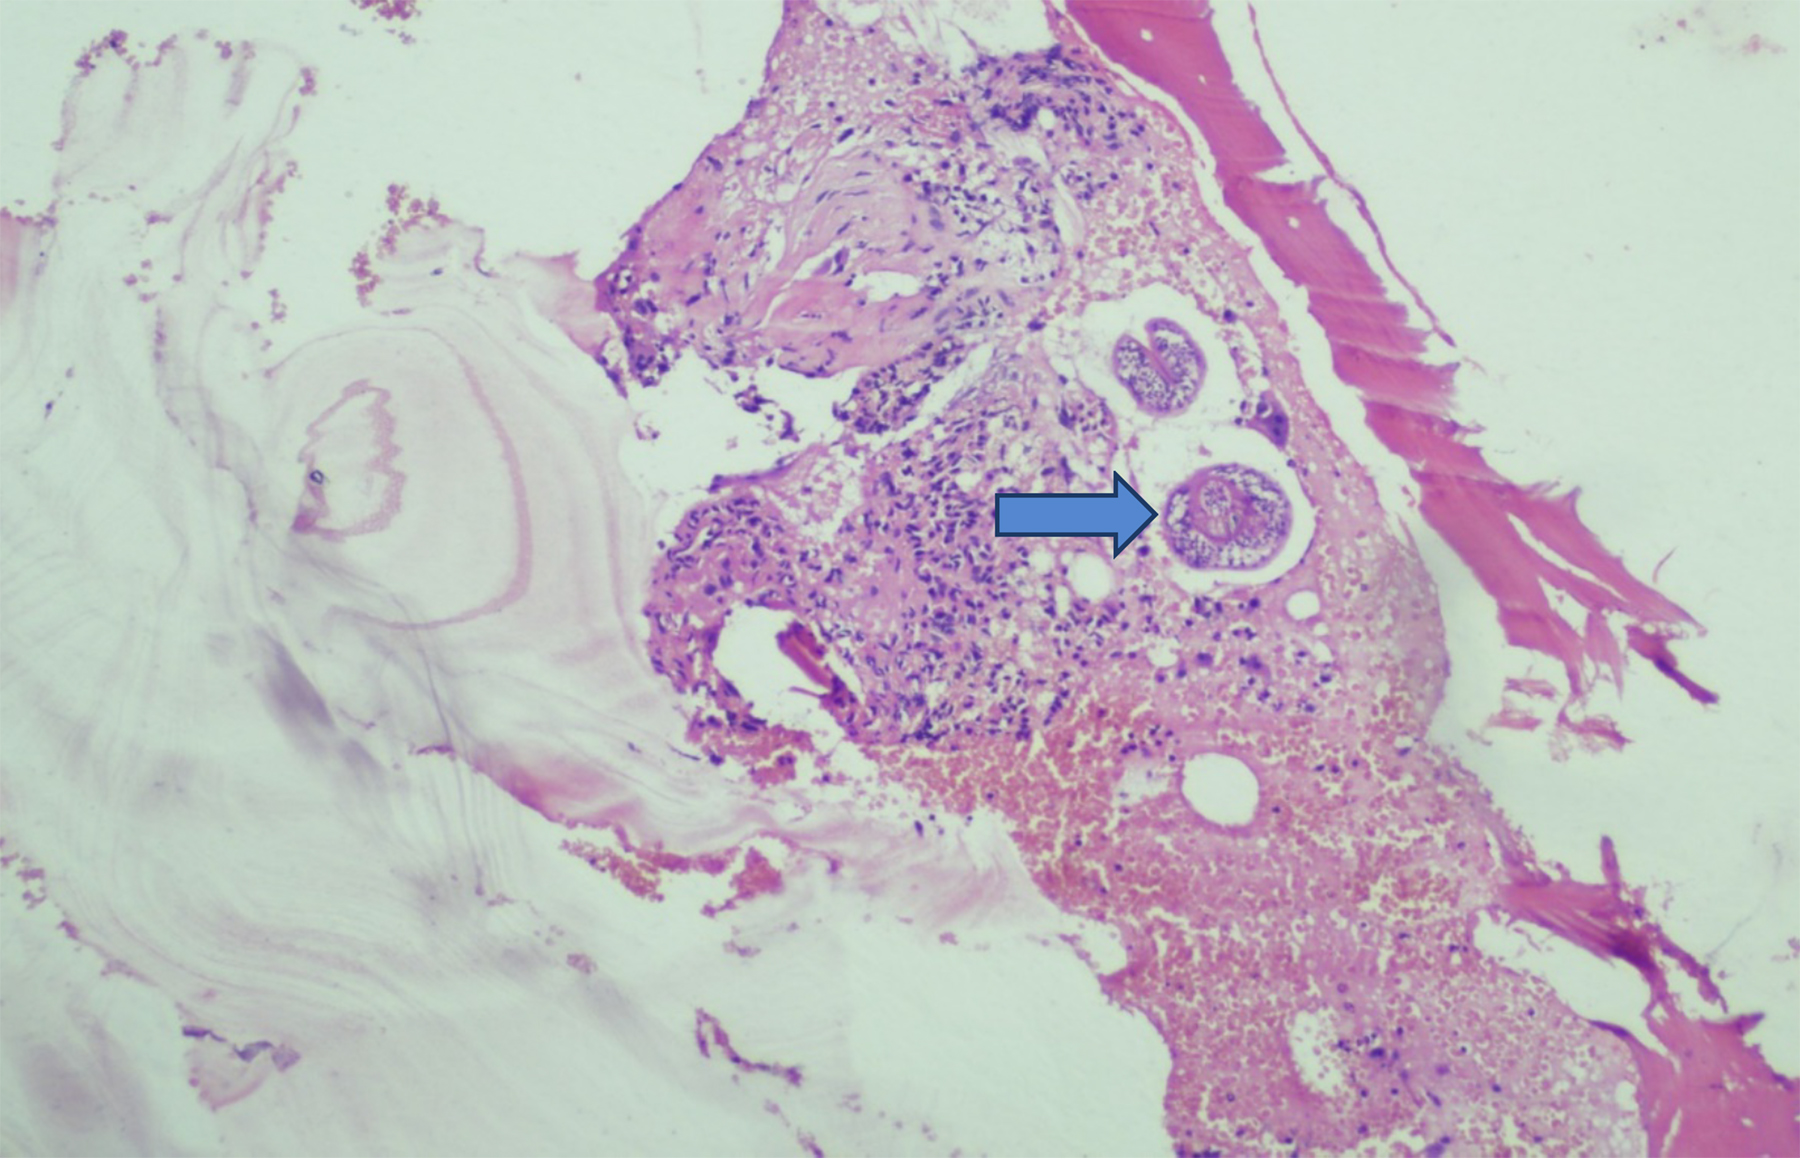

Histopathological examination of the excised tissue revealed the presence of laminated membranes and scolices (Figure 1), confirming the diagnosis of a hydatid cyst. The cyst wall exhibited a characteristic three-layered structure: an outer fibrous capsule, a middle layer containing a laminated and acellular material, and an inner germinal layer with protoscolices (Figure 2). These findings are crucial for differentiating hydatid disease from other cystic lesions.

Figure  1:  High-power view showing cyst contents, laminated and acellular material, in between the bone trabeculae.